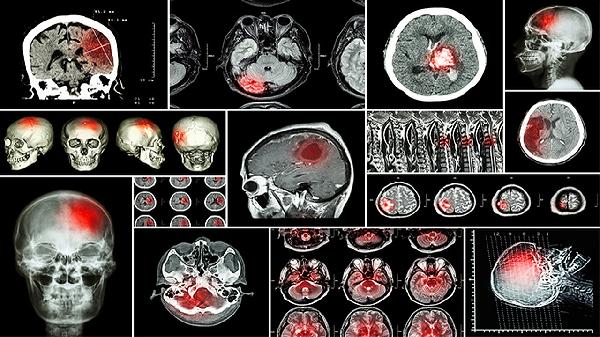

开放性脑损伤神经系统体征有哪些

开放性脑损伤的神经系统体征主要有意识障碍、运动功能障碍、感觉异常、瞳孔变化以及语言障碍等。开放性脑损伤是指颅骨骨折导致脑组织与外界相通的损伤,可能由外伤、交通事故、高处坠落等因素引起,需及时就医处理。